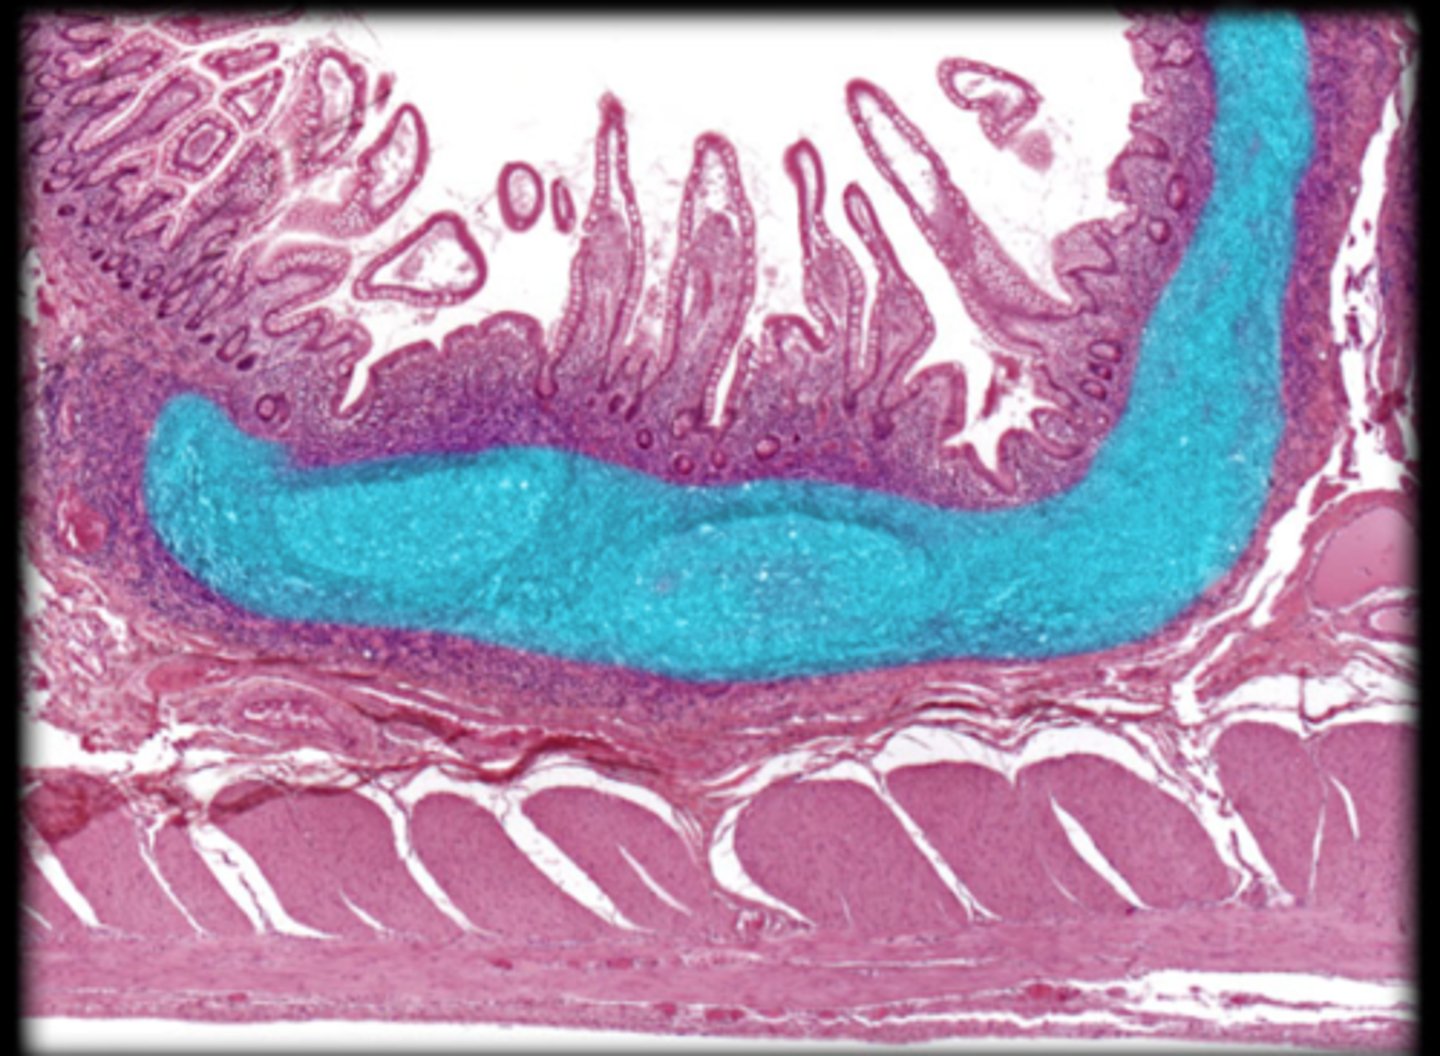

ileum

Peyer's patches are only in the _________ of the small intestine.

peyer's patch of ileum

Small intestine

Vermiform appendix